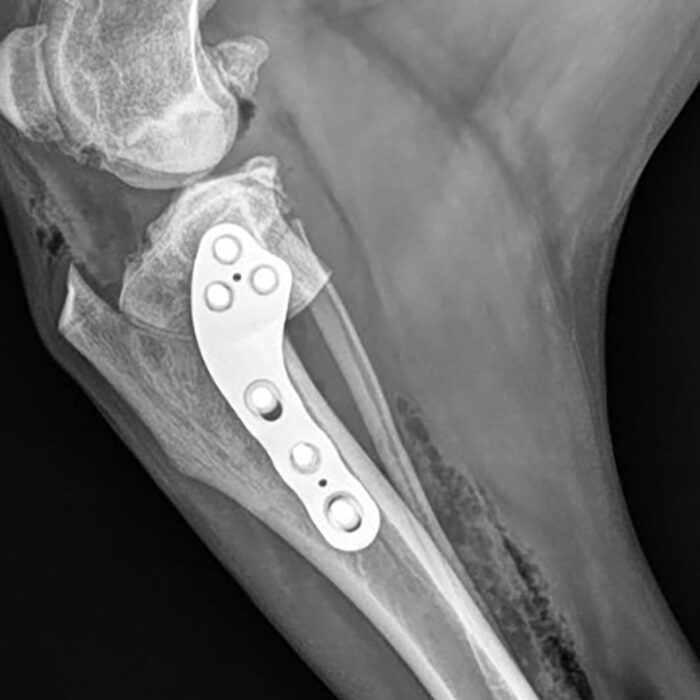

A hands-on course with Dr Yves Samoy, teaching cranial closing wedge technique for cruciate surgery, featuring the Rita Leibinger CCWO titanium polyaxial plate. This course is priced at £995+VAT. Lunch and refreshments are provided throughout the day. Please create your booking by clicking...